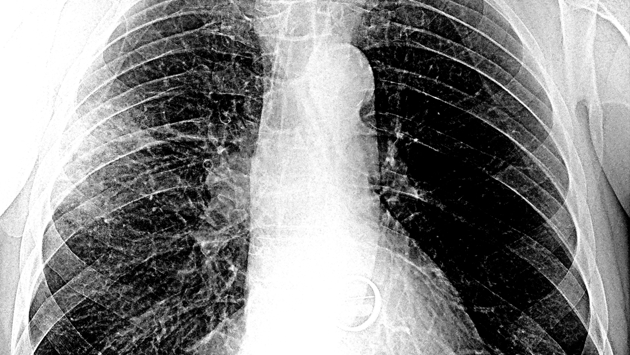

Учёные: «Омикрон» быстрее вызывает пневмонию по сравнению с другими штаммами коронавируса

По словам эксперта, у «Омикрона» эффективные механизмы присоединения к рецепторам и проникновения в клетки человеческого организма. Поэтому он быстрее, чем другие варианты SARS-CoV-2, опускается в лёгкие, вызывая пневмонию. Если при других штаммах от момента заражения до развития пневмонии проходило 10-11 дней, сейчас этот период сократился до 3-5 дней.

При этом «Омикрон» немногим отличается от других штаммов. «Оно меняется и становится более эффективным, но мы пока всего не знаем. Тесты на нейтрализацию вируса занимают достаточно много времени, но биоинформатические исследования уже проведены во многих странах, в том числе и в России. И учёные не нашли ничего такого, что бы ставило свойства вируса с ног на голову. Что плохо в штамме «Омикрон», он точно так же, как и «Дельта», более тропен, то есть способен к взаимодействию с эпителием лёгких — нижних дыхательных путей. Поэтому «Омикрон» быстрее спускается в лёгкие, вызывая пневмонию. Это очень тревожно», — отметил Семёнов.